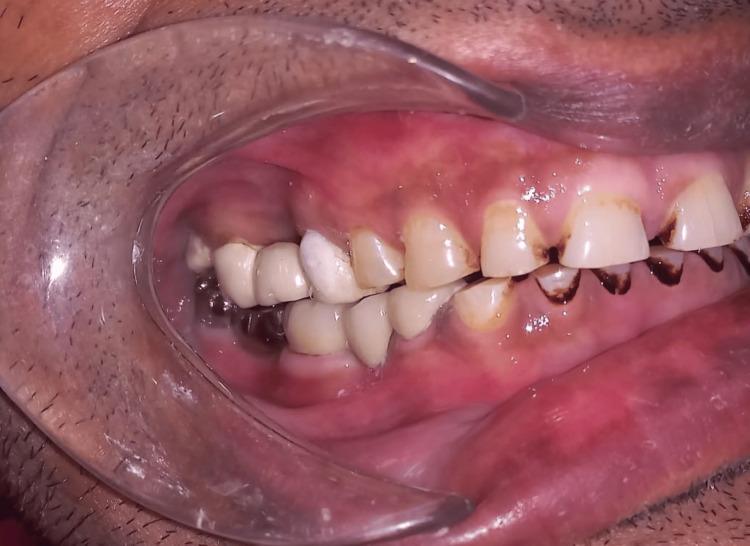

The attachment of a fixed partial denture (FPD) on a pier abutment may be necessary in some partially edentulous instances because of the pattern of lost teeth. Nonetheless, it has been noted that using a stiff FPD to restore two lost teeth and an intermediate pier abutment is not the best course of action. In this case, using a stiff connector concentrates the stresses on the pier abutment. In this situation, the pier abutment serves as a pivot, increasing the debonding of the fixed dental prosthesis and ultimately compromising the success of the FPD. Connectors that are not stiff can solve these issues. A nonrigid connector allows abutments to move independently and distributes shear forces to the supporting bone. Instead of the typical rigid connector, the nonrigid connector serves as a stress breaker between the retainer and the pontic.